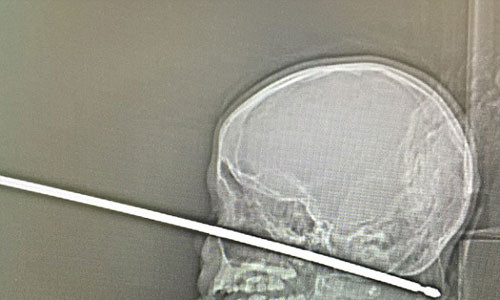

| Xiên xuyên thủng đầu Xavier. |